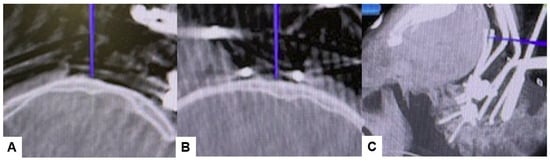

2.4. Surgery

2.5. Postoperative Imaging